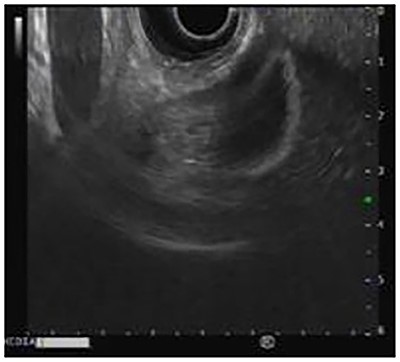

A 22-year-old male with smoking habits was periodically followed in internal medicine consultations for epigastric abdominal pain, in which, through endoscopic examinations, a Helicobacter pylori positive test was identified. Once the eradication of H. pylori was completed and confirmed, the patient started experiencing symptoms of recurrent pain in the right hypochondrium. His blood tests were normal. An abdominal ultrasound was performed, which revealed a nodular image adhering to the internal wall (not moving with positional changes) with 18 mm, found in the infundibular region. It was echogenic with an anechoic center. These aspects were compatible with sessile polyp with a necrotic center associated with surrounding parietal thickening. In order to obtain further clarification, an endoscopic ultrasonography was carried out, which confirmed a homogeneous echogenic lesion with central hypoechogenicity with a larger transversal diameter of 18 mm adhering to the wall (Fig. 1). In this context, the patient was proposed for elective laparoscopic cholecystectomy, which occurred without complications. After surgery, microscopy revealed a cavitated polyp consisting largely of gastric body mucosa, although pyloric type mucosa was still found, with no intestinal metaplasia or epithelial dysplasia being identified (Fig. 2—macroscopic examination/Fig. 3—microscopy).

Endoscopic ultrasound shows an echogenic polyp in the infundibulum of the gallbladder.